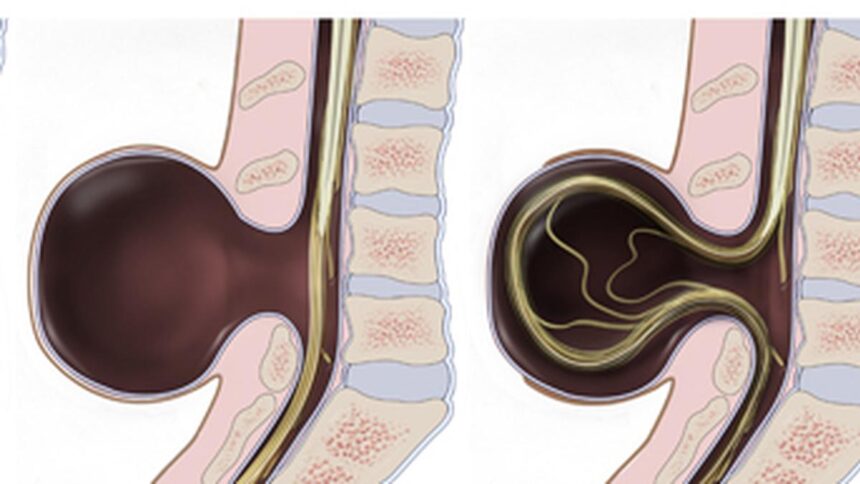

There are three fundamental kinds of spina bifida. Probably the most critical type of this situation is myelomeningocele or open spina bifida. On this sort, a part of the spinal twine and nerves are uncovered via a sac on the opening of the spinal hole. The second sort of meningocele, a much less widespread sort of spina bifida, happens when the meninges, the protecting membranes across the spinal twine, are pressured via a gap in a fluid-filled sac. Normally on this sort, the spinal twine develops usually and the nerves should not affected. The third sort of situation is called spina bifida occulta or “hidden” spina bifida. That is the mildest type of a situation wherein a number of vertebrae don’t kind correctly, making a small hole. Many individuals with this illness have no idea they’ve it as a result of it often doesn’t trigger any signs.

Surgical procedure is one therapy choice. For extreme myelomeningocele, surgical procedure could also be accomplished earlier than start, whereas the newborn remains to be within the womb, or instantly after start. That is accomplished to shut gaps within the vertebrae and defend the growing spinal twine from publicity. Though surgical procedure whereas the newborn is within the womb carries dangers for each mom and child, some researchers imagine it could result in higher outcomes and fewer disabilities for the newborn. Infants with hydrocephalus may have surgical procedure to empty fluid. Some sufferers may want surgical procedure for spinal twine tethering (a situation wherein the spinal twine is connected to the spinal canal reasonably than floating freely).